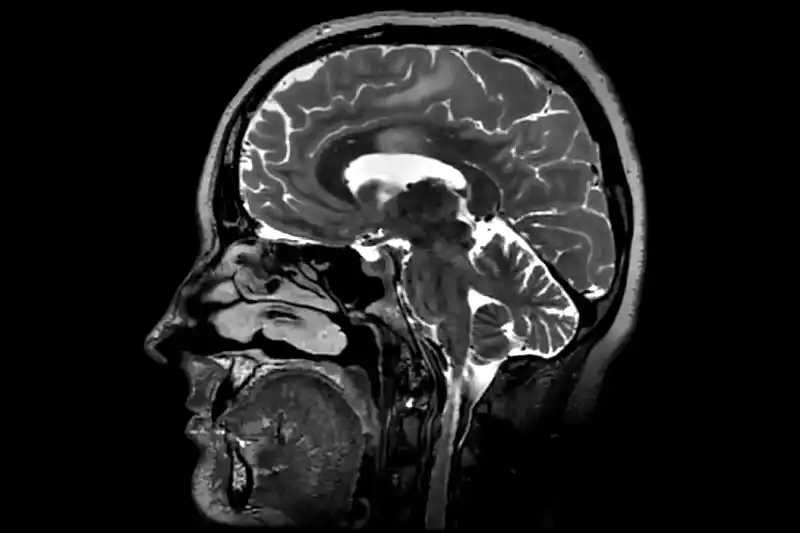

Un estudio con miles de escáneres cerebrales

El equipo analizó a más de 4.000 personas de entre 0 y 90 años, quienes se sometieron a múltiples escáneres para medir cómo cambian las conexiones neuronales a lo largo del tiempo. Alexa Mousley, una de las autoras, explicó a la BBC que el cerebro “se reconfigura durante toda la vida”, en un proceso continuo de fortalecimiento y debilitación de conexiones que avanza por fases claramente diferenciadas.

Aunque los ritmos varían de persona a persona, los investigadores remarcaron que las edades críticas emergieron con una nitidez “sorprendente”.